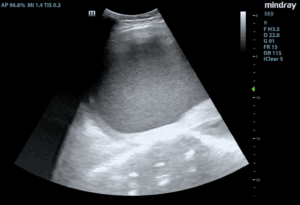

An 82-year-old female with a past medical history of aortic insufficiency and prior surgical history of a right incarcerated femoral hernia repair and incisional hernia repair with mesh placement presented to the ED with abdominal pain, vomiting, and non-bloody diarrhea for the last couple of days. The patient reported diffuse constant abdominal pain, which was worse in the lower abdomen, and decreased oral intake. Upon arrival to the ED, the patient’s blood pressure was 156/81mm Hg, heart rate was 156 beats per minute, respiratory rate was 24 breaths per minute, and temperature was 37.5 degrees Celsius (99.5 Degrees Fahrenheit). On physical exam, the patient was well appearing, tachycardic with an irregular heart rate. The patient’s abdomen was soft, diffusely tender to palpation, with normal bowel sounds and no peritoneal signs. Abdominal POCUS was performed, which showed bowel wall thickening of 0.54 cm (Figure 1a) and free fluid surrounding an area of thickened bowel with enhancement of pericolonic fat (Figure 1b).

Figure 1. (a): A point of care ultrasound (POCUS) image of the lower abdomen using a curvilinear probe showing a thickened and edematous bowel wall (arrow) and enhancement of the pericolonic fat (star). (b): A point of care ultrasound (POCUS) image of the lower abdomen showing a dilated loop of bowel by the bladder (star) with evidence of free-fluid (arrow) and enhancement of pericolonic fat.